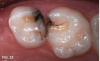

Case 4. At his first dentistry appointment, a 5-year-old with dentinogenesis imperfecta had large caries lesions on the distal of both mandibular primary first molars (Figure 12), along with smaller caries lesions on the distal of the maxillary right primary canine tooth and distal surface of the maxillary right first molar. The distal marginal ridge of the mandibular left second primary molar was fractured and subsequently trimmed smooth, but there was no caries detected in the exposed dentin. Stainless steel crown restoration of the primary first molars would have been difficult to accomplish because of the anatomical form of those teeth, the amount of wear/erosion of the maxillary first molars, and severity of carious destruction of the mandibular first molars. It was predicted that those teeth would be lost to extractions prior to their normal exfoliation time, therefore the goal was to preserve the teeth in place until eruption of the permanent molars to facilitate eventual space maintenance planning. It was thought that SDF could provide an immediate interim solution for caries control for this child, and after this was explained, the boy's father agreed to that treatment immediately at that visit. With cotton roll isolation, top layers of carious tooth substance were debrided from the mandibular first molars using a slow-speed round bur (Figure 13). No anesthetic injections were needed, and the patient related no discomfort. SDF was then painted on the caries lesions of the four teeth (Figure 14), followed by fluoride varnish application (Figure 15). The patient was seen several weeks later for renewed SDF application and dental prophylaxis (Figure 16 and Figure 17).

Fig 16. Several weeks later, caries lesions are dark black.

Fig 16

Fig 17. Several weeks later, caries lesions are dark black.

Fig 17